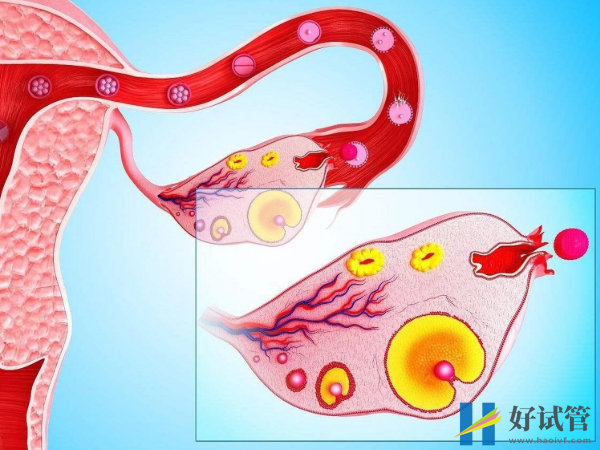

在备孕期间,什么时候查优势是很重要的,因为当测到优势卵泡后,就意味着大概率可以正常的排卵。通常测到优势卵泡后的3-5天就会排卵,至于优势卵泡排出后可以维持几天,以及有优势卵泡是否就能怀孕等相关疑问,下文是整理了一些相关信息,想了解更多的便可查看。

测到优势卵泡3-5天后会排卵

当优势卵泡发育成熟后,从卵巢中排出会在体内存活48小时左右,也就是两天。所以在这两天的时间里面就可以同房,这样是可以提高受孕的几率。在这48个小时之内,前二十四个小时的受精能力是最强的,后二十四个小时的受精能力就会有所下降直到死亡。而进行同房前男方也需要禁欲,这样才能提高精子的质量,进而增加受精几率。

优势卵泡成熟排卵时同房能提高受孕几率

通常精子的存活期比较长,在输卵管的七十二小时之内都有受精的能力,所以在排卵前后都可以同房。如果是做试管婴儿的患者,那么对于优势卵泡会存活几天就不用过多在意,因为做试管婴儿的时候会同时将卵子和精子取出体外,所以取出后就会拿去实验室培育受精卵,所以就不用担心受精的问题。